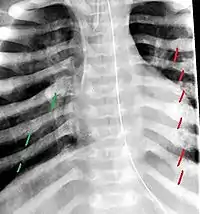

The material factual allegations of the amended complaint are as follows. Plaintiff was born on May 14, 1970. On repeated occasions during the first year of her life she was severely beaten by her mother and the latter's common law husband, one Reyes. On April 26, 1971, when the plaintiff was eleven months old, her mother took her to the San Jose Hospital for examination, diagnosis, and treatment. The attending physician was defendant Dr. Flood, acting on his own behalf and as agent of the defendant San Jose Hospital. At the time, the plaintiff was suffering from a comminuted spiral fracture of the right tibia and fibula, which gave the appearance of having been caused by a twisting force. Plaintiff's mother had no explanation for this injury. Plaintiff had bruises over her entire body. In addition, she had a non-depressed linear skull fracture which was then in the process of healing. Plaintiff demonstrated fear and apprehension when approached. Inasmuch as all plaintiff's injuries gave the appearance of having been intentionally inflicted by other persons, she exhibited the medical condition known as the battered child syndrome.

The complaint avers that as a proximate result of the foregoing negligence plaintiff was released from the San Jose Hospital without proper diagnosis and treatment of her battered child syndrome, and was returned to the custody of her mother and Reyes who resumed physically abusing her until she sustained traumatic blows to her right eye and back, puncture wounds over her left lower leg and across her back, severe bites on her face, and second and third degree burns on her left hand.

On July 1, 1971, plaintiff was again brought in for medical care, but to a different doctor and hospital. Her battered child syndrome was immediately diagnosed and reported to local police and juvenile probation authorities, and she was taken into protective custody. Following hospitalization and surgery she was placed with foster parents, and the latter subsequently undertook proceedings to adopt her. Plaintiff's mother and Reyes fled the state, but were apprehended, returned for trial, and convicted of the crime of child abuse.[3]

For example, the leading article by Kempe et al., op. cit., supra,[11] states that "A physician needs to have a high initial level of suspicion of the diagnosis of the battered-child syndrome in instances of subdural hematoma, multiple unexplained fractures at different stages of healing, failure to thrive, when soft tissue swelling or skin bruising are present, or in any other situation where the degree and type of injury is at variance with the history given regarding its occurrence . . . ." (Id., at p. 20.) Of the different types of fractures exhibited, an arm or leg fracture caused by a twisting force is particularly significant because "The extremities are the 'handles' for rough handling" of the child by adults. (Id., at p. 22.) The article also contains numerous recommendations to conduct a "radiologic examination of the entire skeleton" for the purpose of confirming the diagnosis, explaining that "To the informed physician, the bones tell a story the child is too young or too frightened to tell." (Id., at p. 18.) Finally, on the subject of management of the case it is repeatedly emphasized that the physician "should report possible willful trauma to the police department or any special children's protective service that operates in his community" (id., at p. 23) in order to forestall further injury to the child: "All too often, despite the apparent cooperativeness of the parents and their apparent desire to have the child with them, the child returns to his home only to be assaulted again and suffer permanent brain damage or death." (Id., at p. 24.)